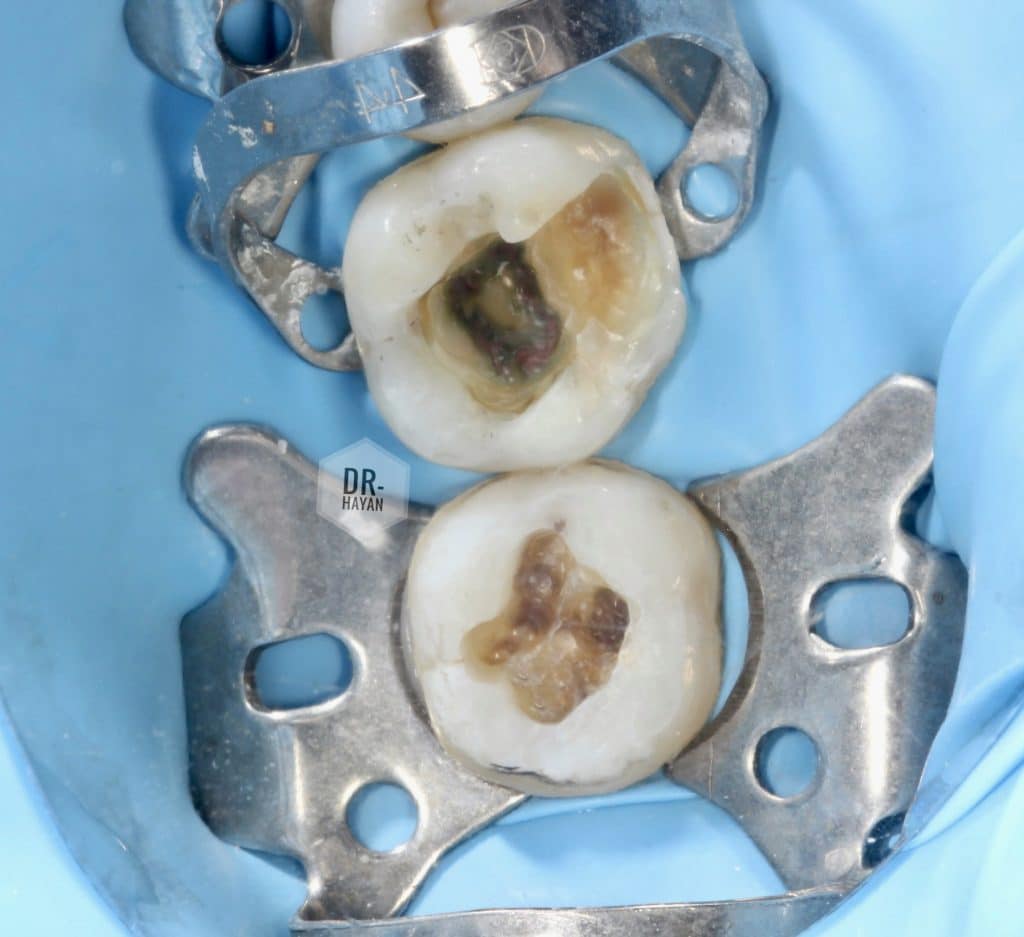

Pre operative examination :

Percussion - - -

Palpation - - -

Cold test + + +

Peri apical X ray normally

- Amalgam removal should be done under full isolation

- Must have face shield or eye goggles

- should be removed by stone not Not carbide bur

As carbide will produce amalgam ships

After that:

-remove the caries with round bure

-apply CDD

44 clamps for mor inversion the tissue

After complete soft caries removal

Amalgam tattoo & hard discoloration dentine on floor of cavity

No need for remove it :